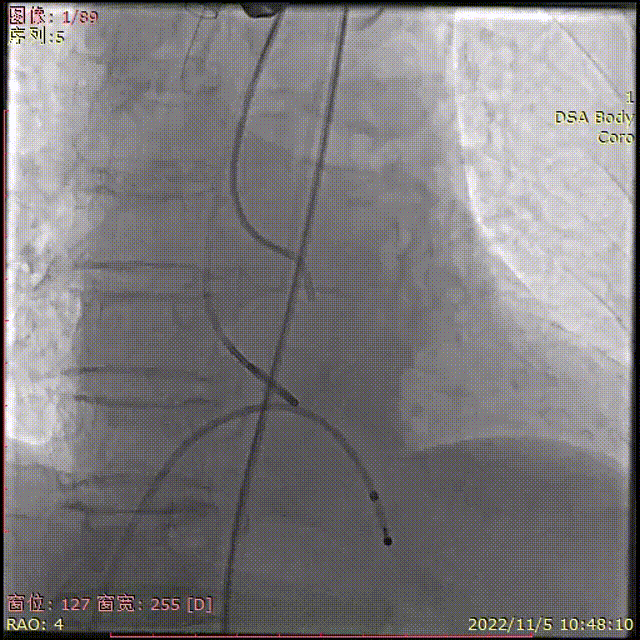

导丝顺利跨瓣

TaurusElite输送器顺利过弓